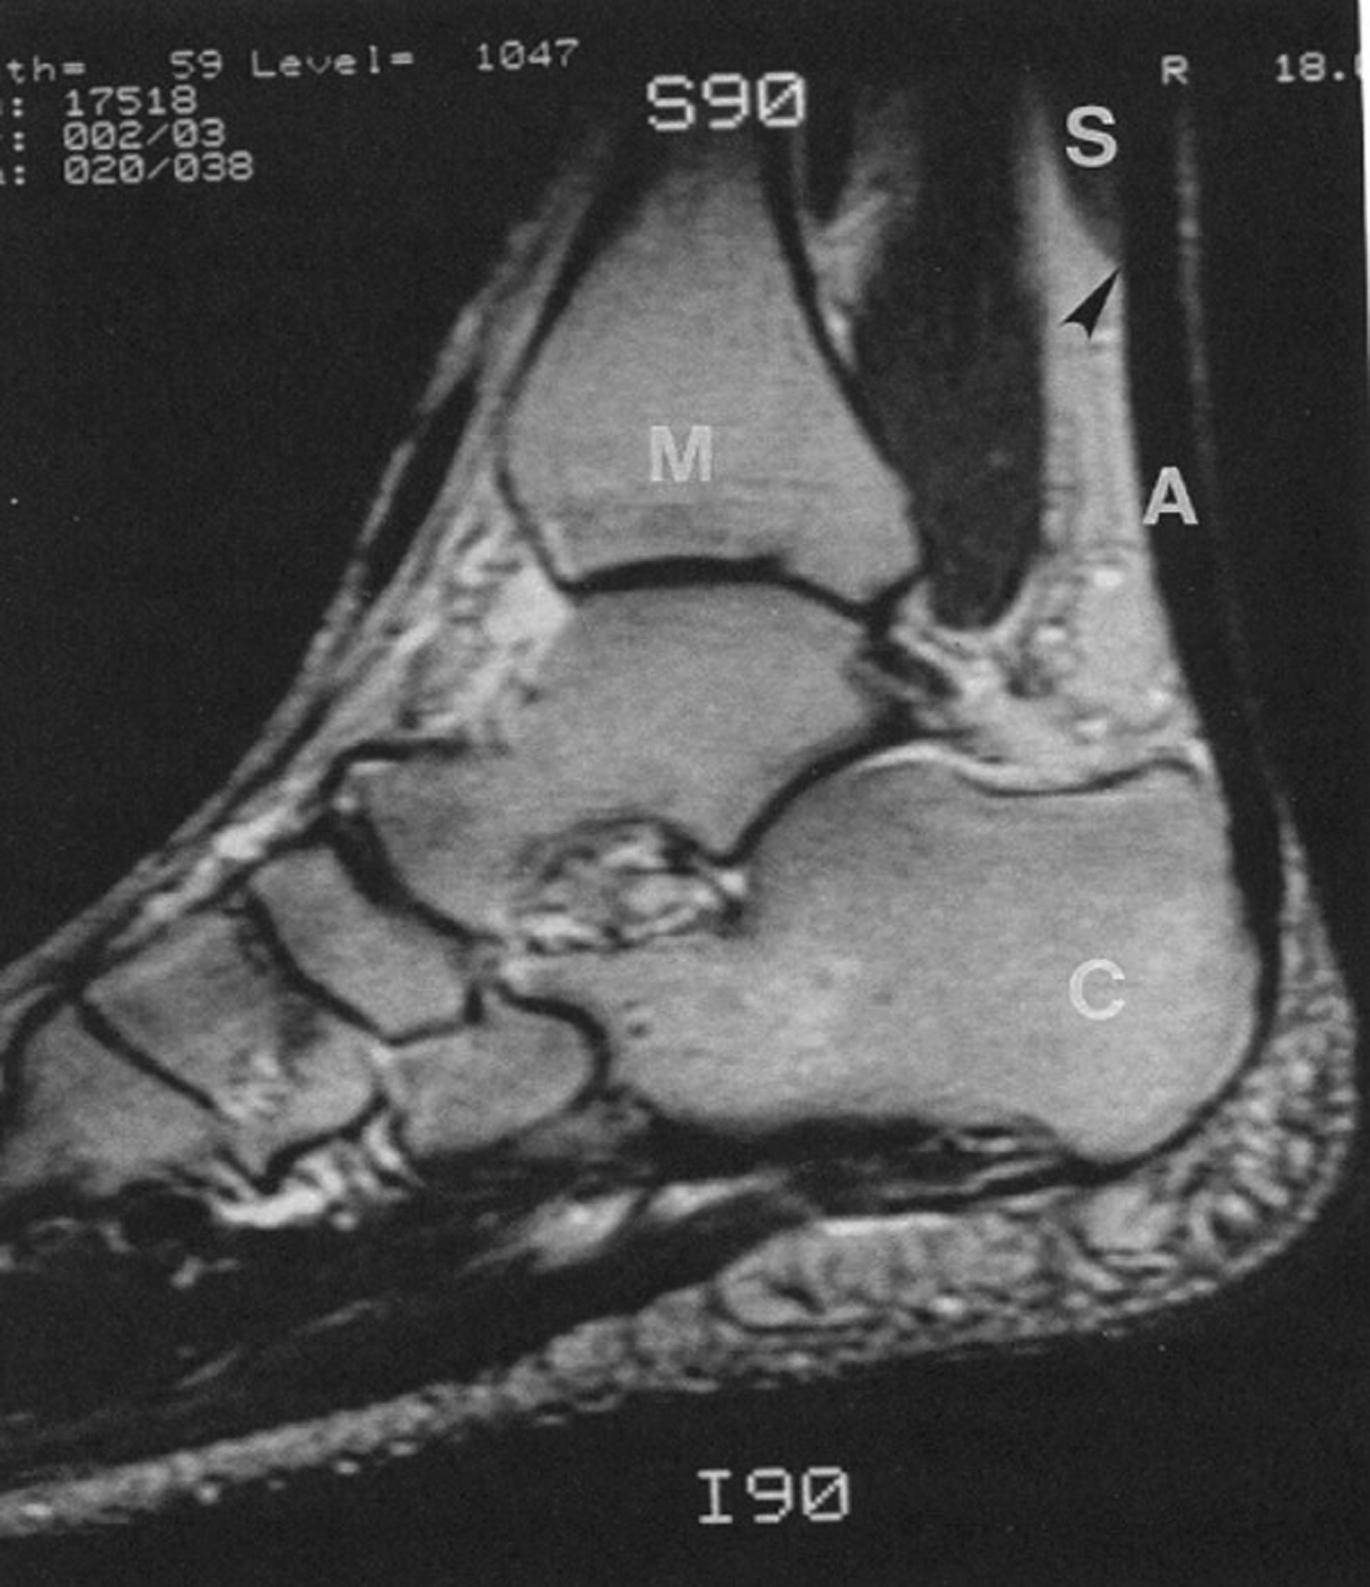

This author prefers an intraoperative dissection of the soleus muscle to confirm the level of the distal muscle insertion, although a preoperative MRI can easily identify the location of the soleus musculotendinous junction in the ankle. Once the medial hemisoleus muscle is identified and dissected freely to the level at the junction between the middle and distal thirds of the tibia, the major perforators from the posterior tibial vessels to the medial half of the soleus muscle within even distal third of the tibia should be identified ( Fig. 7 ). Next, the surgeon must be attentive in the preservation of these perforators when designing the adequate arc of flap rotation to cover the target soft tissue defect or exposed hardware ( Fig. 8 ). If needed, the medial hemisoleus muscle can be extended more laterally after longitudinally splitting, so that the flap can be made wide enough to cover a relatively large wound in the distal third of the leg. These modifications made by the author to the surgical techniques in flap dissection emphasize the preservation of an adequate blood supply to the distal portion of the medial hemisoleus muscle flap after flap elevation. These techniques maximize the reliability of the medial hemisoleus muscle flap and expand its role in reconstruction of distal third tibial wounds , , , ( Fig. 9 ).